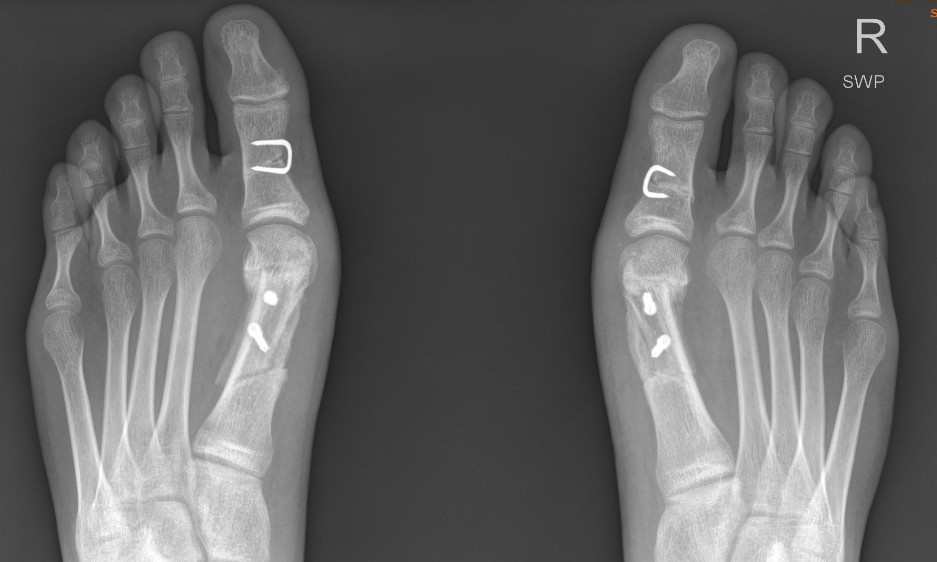

Osteotomy

Akin / proximal phalangeal osteotomy - corrects interphalangeal angle

Chevron / Scarf osteotomy

Proximal metatarsal osteotomy

Double osteotomy - proximal and distal

Lapidus procedure

Indications

- hypermobility of the TMT joint

- obliquity of the first TMT joint

1st Cuneiform Opening Wedge Osteotomy

Severe IM angle with open 1st metatarsal epiphysis

- marked M-C joint obliquity with high IM angle

- opening wedge (iliac crest graft)